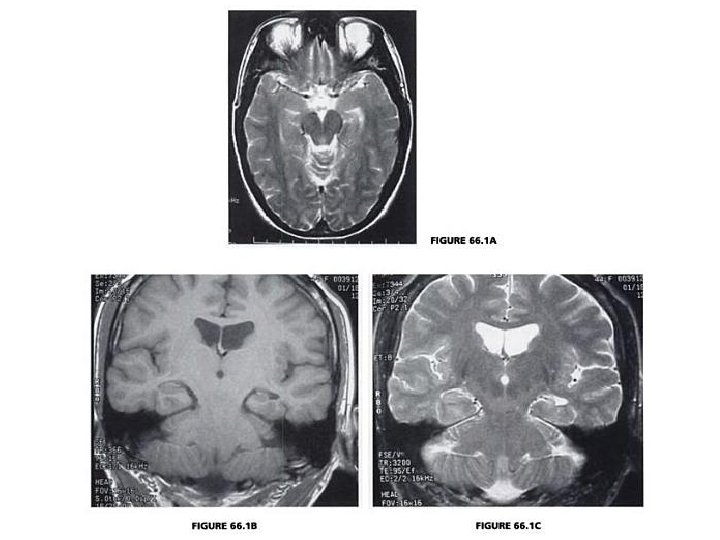

MANAGEMENT Examination �Obs, Cadio, Respiratory, Abdo �Neuro UL, LL and CNs Investigations �Bedside: Bloods, BM, Urine dip, (BCM) �EEG �Radiology: consider CT, MRI for new epileptic ? tumours ? hippocampal sclerosis